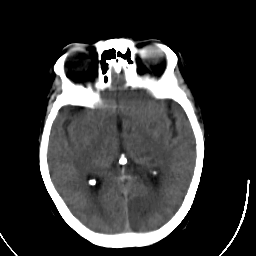

Stroke CT #3 -- Slice #11

[Home][Help][Clinical] Slice 11